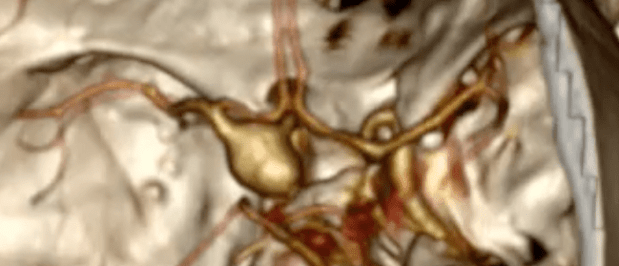

Aneurisma cerebral é uma dilatação das artérias do cérebro. Artérias são os vasos sanguíneos que levam o sangue ao cérebro, em contraste aos vasos que levam o sangue do cérebro de volta ao coração, que são chamados de veia. Este sangue é bombeado pelo coração, sob pressão, e levam nutrientes para o cérebro funcionar normalmente.

Este “encanamento” que leva o sangue pode ficar doente e suas paredes podem acabar se dilatando, formando por vezes pequenos sacos, parecidos com bexigas, contendo esse sangue sob pressão.

- Clipagem microcirúrgica – nesta modalidade é colocado um clipe por fora do aneurisma

- Embolização endovascular – nesta modalidade é colocado molas e/ou stents por dentro do aneurisma